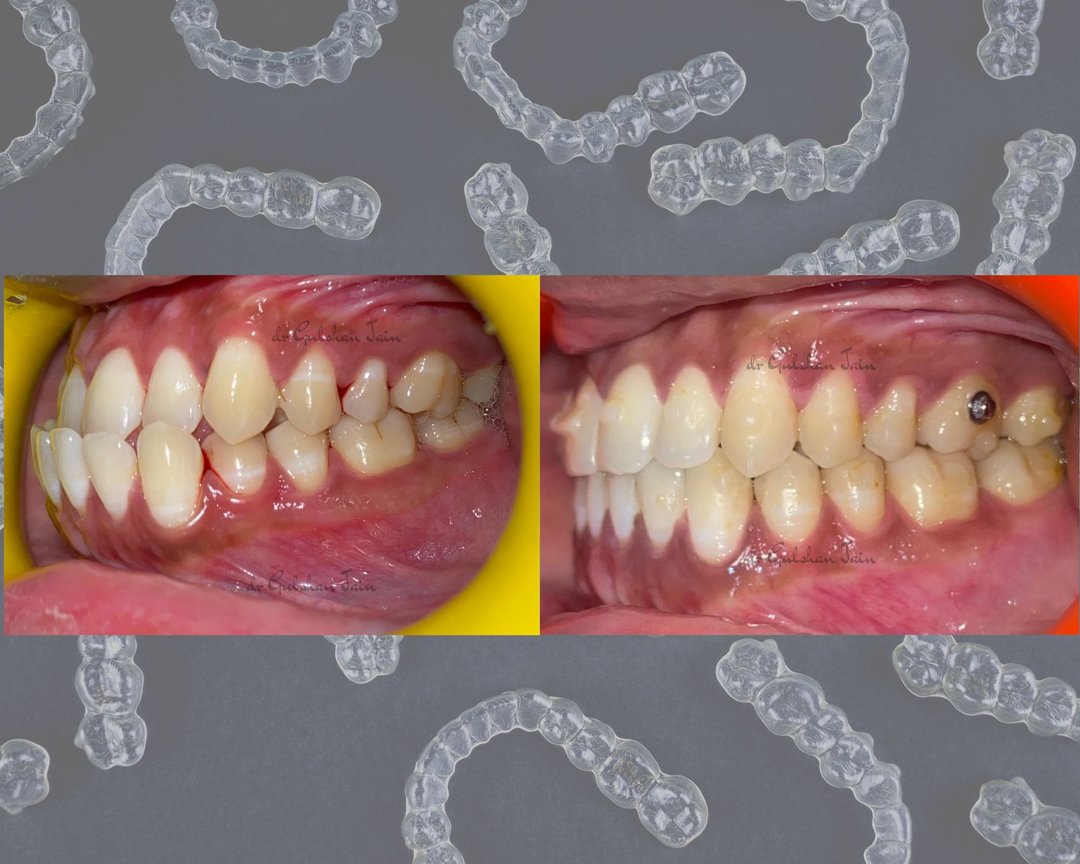

Welcome to our gallery

See how our company transforms ideas into reality. This gallery is a visual testament to our work and achievements.